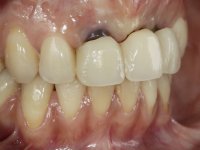

Paciente do sexo feminino, com 30 anos de idade, não fumadora. A paciente surge na consulta após tratamento ortodôntico e colocação de um implante no local do dente 2.1. Apresentava os dentes 3.7, 3.6 e 4.7 com tratamento endodôntico e os dentes 1.5, 2.5, 2.6 e 4.5 com restaurações extensas. Apresentava um periodonto fino e mostrava uma higiene oral satisfatória. Após exposição cirúrgica do implante este mostrou-se posicionado de forma inadequada. A reabilitação protética do implante mostrou-se impossível adotando critérios estéticos aceitáveis. A paciente durante 6 anos andou com uma coroa provisória de acrílico sobre um coto aparafusado como solução de recurso já que não aceitou a proposta de remover o implante. Após este tempo surge na consulta com um abcesso no dente 1.1. Analisada a situação constatou-se que os dentes 1.1 e 2.2 tinham extração indicada e o implante deveria ser removido ou submergido.

Na fase inicial, foi proposto à paciente fazer a exposição cirúrgica do implante e após avaliação clínica tomar decisões protéticas. Colocado o parafuso de cicatrização e feita a cicatrização dos tecidos moles, foi constatada uma posição inadequada do implante. Perante o dramatismo da situação foi proposto à paciente a remoção do implante e após regeneração tecidular colocar um novo implante. Esta proposta foi recusada pela paciente e foi sugerido por esta a reabilitação provisória do implante. Nesse sentido foi então feita nova proposta, desta feita, reabilitando o implante. Foi sugerido a confeção de um coto aparafusado e sobre este a colocação de uma coroa de acrílico com componente coronário e gengival. Passados 6 anos com o tratamento provisório a paciente surge na consulta com um abcesso no dente 1.1. Feita a análise clínica e imagiológica decidiu-se extrair os dentes 1.1 e 2.2, submergir o implante, colocar dois implantes no local dos 1.1 e 2.2 e fazer regeneração tecidular adequada. A temporização seria feita com uma ponte provisória de 3 elementos aderida com uma rede aos dentes vizinhos. Após osteointegração seria reabilitada definitivamente com uma ponte de 3 elementos, com infraestrutura de Zr revestida a cerâmica.

A exposição cirúrgica do implante e a colocação do parafuso de cicatrização mostrou-se uma surpresa negativa no que diz respeito à sua posição. Rejeitada a proposta de remoção do implante, avançamos para a sua reabilitação provisória. Foi feita a impressão por técnica de moldeira aberta e em laboratório foi confecionado um coto aparafusado com componente gengival e coronário e uma coroa em acrílico também com estes dois componentes. A coroa provisória foi colocada em boca até ser tomada uma decisão definitiva. Passaram 6 anos até que a paciente retorna à consulta com um abcesso no dente 1.1. Tomada a decisão de extrair os dentes 1.1 e 2.2 foi feita uma impressão para confecionar uma ponte provisória de 3 elementos com uma rede para ser aderida aos dentes adjacentes. A cirurgia foi planificada e realizada, colocando-se os dois implantes no local do 1.1 e 2.2 e o implante no local do 2.1 foi cortado com o objetivo de o submergir, simultaneamente foi feita a regeneração tecidular adequada (Trabalho Cirúrgico realizado por Dr. Manuel Neves). Durante a osteointegração a paciente utilizou a ponte provisória fixa. Foi realizada primeira impressão para a confeção de uma ponte provisória aparafusada em Zr que trabalhou durante 12 semanas os tecidos moles. A impressão definitiva foi feita com a individualização dos transferes. A reabilitação definitiva foi feita com cotos ceramizados e com uma ponte de infraestrutura em Zr revestida por cerâmica. Em virtude da inclinação do implante colocado no local do dente 1.1 a ponte exigiu fixação cimentada.